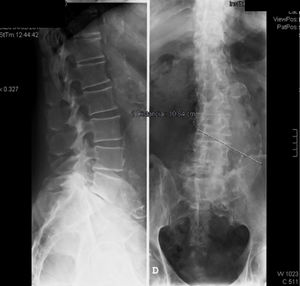

In physical examination of his spine, we observed minimum scoliosis, negative pressure in the lumbar spine, limitation in flexion and extension in the final stages, with no other abnormalities, and a normal neurological examination. Plain radiology revealed lumbar scoliosis, minor listhesis of less than 20% of L5 over S1, with disk disease, vacuum phenomenon and posterior sclerosis suggestive of arthrosis. The abdominal aorta was calcified, with a considerable dilatation caused by an aneurysm measuring approximately 10cm in diameter (Fig. 1).

Given this finding, the patient underwent vascular surgery within the next 48h, with disappearance of the mixed low back pain. Urgent laboratory tests had been performed prior to the operation. They showed a hemoglobin level of 10.3g/dL, with normal mean corpuscular volume and mean corpuscular hemoglobin; platelet levels and coagulation studies were normal. We found nothing abnormal in the liver function. Serum creatinine was 1.3mg/dL.

We performed computed tomography of the lumbosacral spine, that showed bilateral spondylolysis in L5 with grade 1 anterolisthesis of L5 on S1. The remaining vertebral bodies had conserved alignment, height and morphology. The diagnosis was L5-S1 interapophyseal osteoarthritis with degenerative disk disease. We observed interbody fusion, vacuum phenomenon and subchondral sclerosis in endplates. Small left posterolateral protrusion that was in contact with the thecal sac. The patient underwent aortoiliac repair secondary to treatment of abdominal aneurysm.